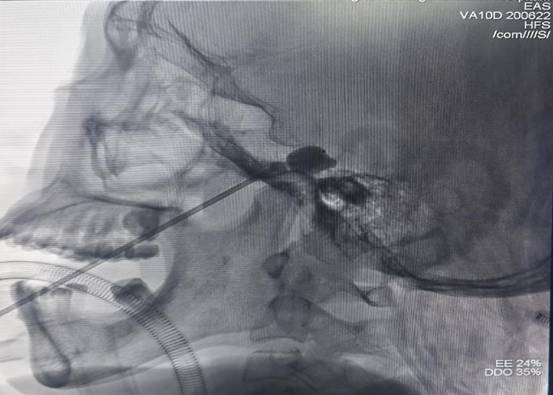

为了解决这一问题,王阿姨来到湘南学院附属医院神经外科,找到科室主任罗忠平教授寻求帮助。“三叉神经痛的治疗方式包括药物治疗和手术治疗,当药物治疗的疗效减退或者出现患者无法耐受的药物副作用而导致药物治疗失败时,可以考虑外科手术治疗。”罗忠平介绍说,“外科手术方式有多种,其中三叉神经半月节球囊压迫术只需要在距离嘴角3cm左右位置穿入一根针,即可完成手术,相较于传统的开颅手术治疗而言具有创伤小、恢复快、不留疤、医疗费用抵等诸多优势,对于高龄、基础疾病多的患者来说,不失为一种相对安全且有效的治疗手段。”完善手术准备后,罗忠平团队为王阿姨实施了左侧三叉神经半月神经节球囊压迫术,术后患者疼痛明显改善。